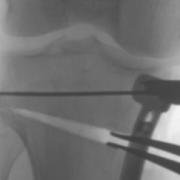

Laminar spreaders open the wedge of a high tibial osteotomy, and then the bone is held in the new position with a plate and screws until new bone fills the gap. Strong metal or carbon fibre plates and screws are used fix the bones in the new position, until new bone heals the defect, after which time the surgeon and patient may elect to remove the plate.